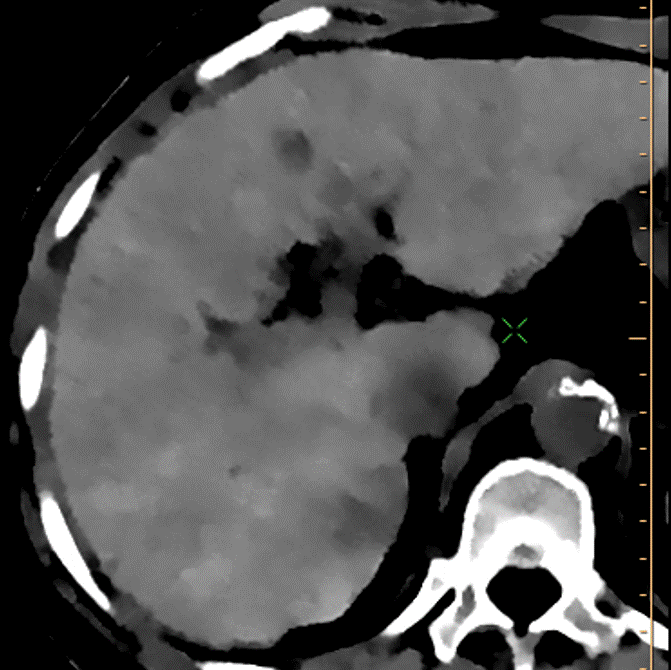

Conventional CT, arterial phase, higher up in the liver. This is unremarkable.

Arterial phase, 40 keV image. See the 2 dots of enhancement?

Delayed phase, electron density: The lesion shows up very well. Again, not sure this qualifies as true washout. In any case there is no capsule. I gave this a LiRADS 4, suspicious for HCC.